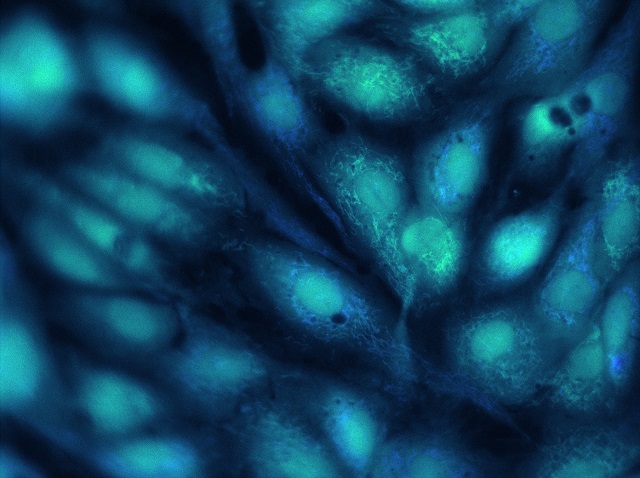

Cells that line the walls of blood vessels, similar to those that will be used in this research.

Dr Jones explains: “The trigger for blood clot formation is damage to the blood vessel wall, caused when fatty plaques break open, or the surface of the blood vessel wall detaches, exposing blood to the ‘sticky’ proteins, which lie beneath. In this study, we will develop materials to recreate these sticky surfaces, and we will be covered these with endothelial cells - the cells that line the blood vessels. We will then damage the endothelial cells to trigger blood clot formation, simulating atherothrombosis. This will enable us to improve our understanding of how blood clots that cause heart attacks and strokes develop, as well as testing out new drugs to treat patients.”